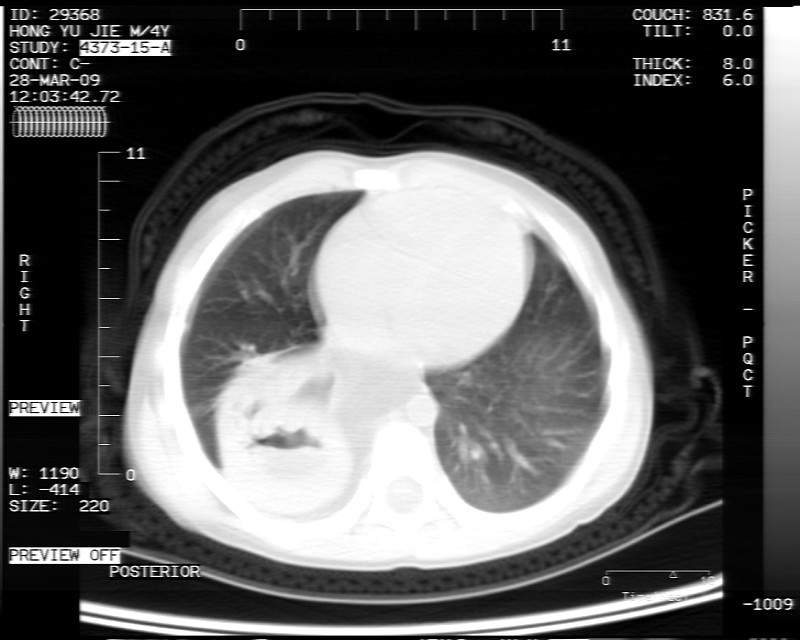

男性,3岁,斜疝术前常规检查胸片体检发现右下肺病变。咳嗽,无发烧。

象腹腔的东西,考虑膈疝

膈疝的表现

内有气体,液平面,考虑食管裂孔疝可能性大。建议食道钡透。

有液气平面,前部肺纹理聚集(受压改变),周围肺野及相邻胸膜清晰,支持膈疝,可吞服造影剂看一下。

考虑膈疝(右侧胸腹膜裂孔疝?)。